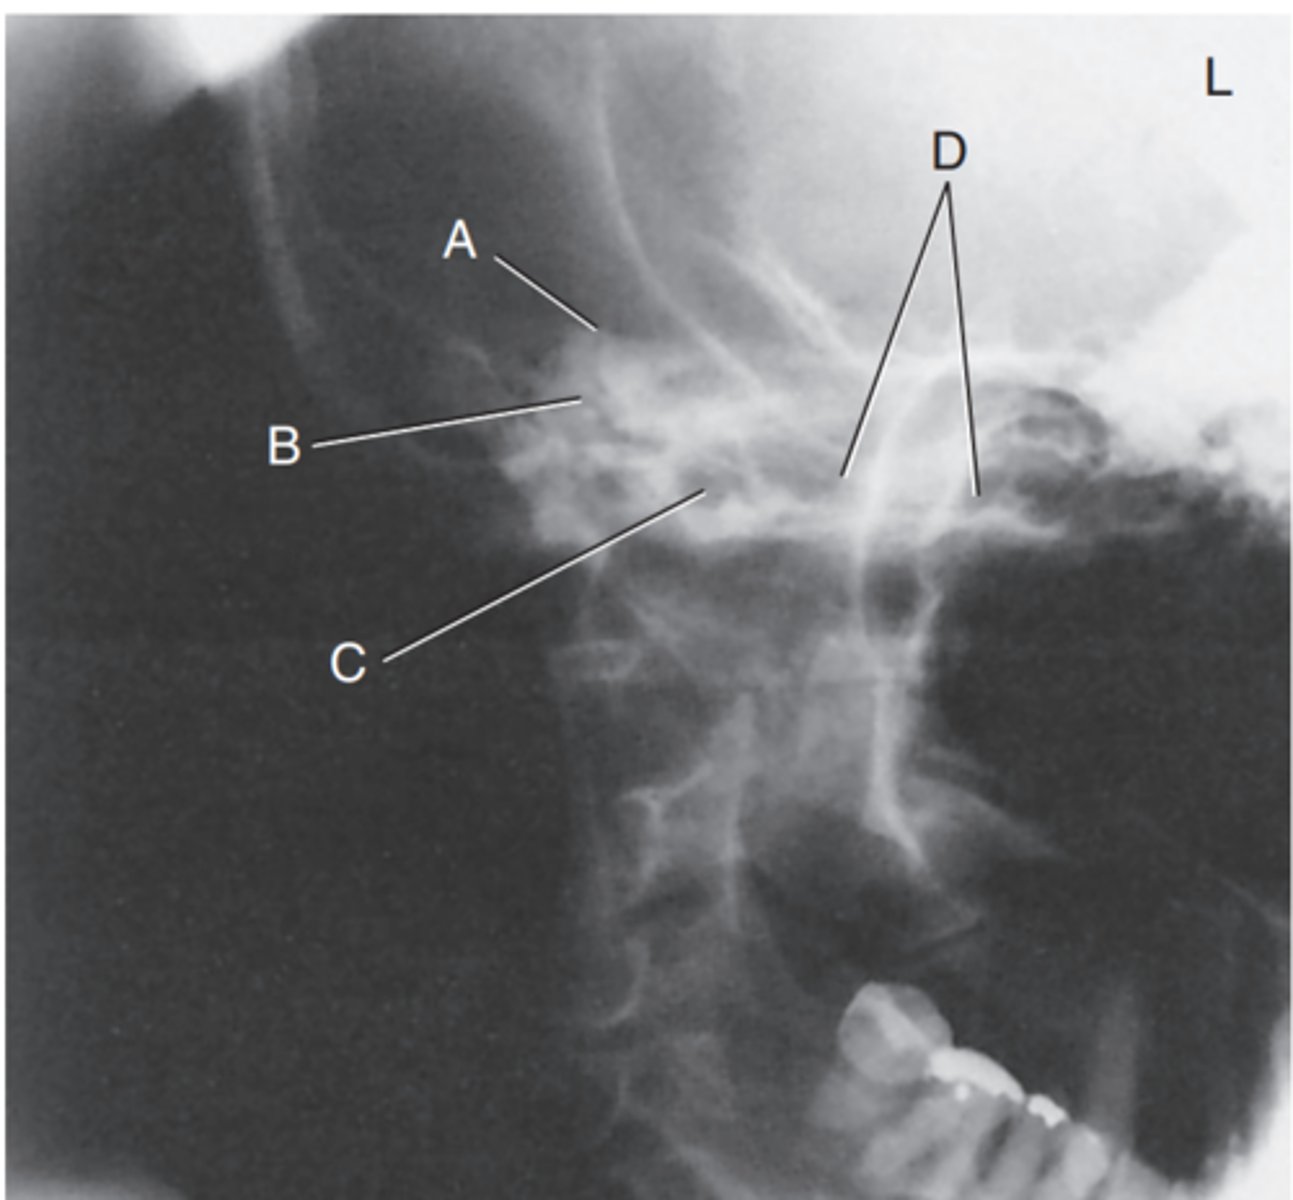

Label A

Mastoid antrum

Label B

Mastoid air cells

Label C

Downside mandibular condyle (just anterior to EAM)

Label D

Upside (magnified) mandibular condyle

Label E

Petrous ridge

Label A

Bony (osseous) labyrinth (semicircular canals)

Label B

EAM

Label C

Region of internal acoustic canal

Label D